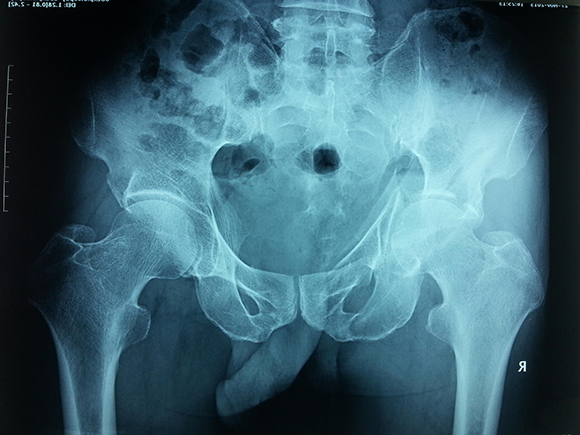

燕化医院开展手术治疗四肢、骨盆骨折患者取得了良好的效果。股骨颈骨折一般以全髋关节置换(THA)和半髋关节置换为主;而对于股骨转子间骨折的外科治疗多采用内固定手术,包括锁定钢板;动力髋系统即DHS、PFN(A)。具有创伤小(微创)、内固定牢固、术后恢复快便于提早下地活动等优点。肱骨、尺桡骨、股骨干、胫骨干的骨折主要采用带锁髓内钉和锁定钢板治疗;复杂的骨盆骨折则采用切开复位,重建钢板治疗。

图3. 复杂的骨盆骨折术前